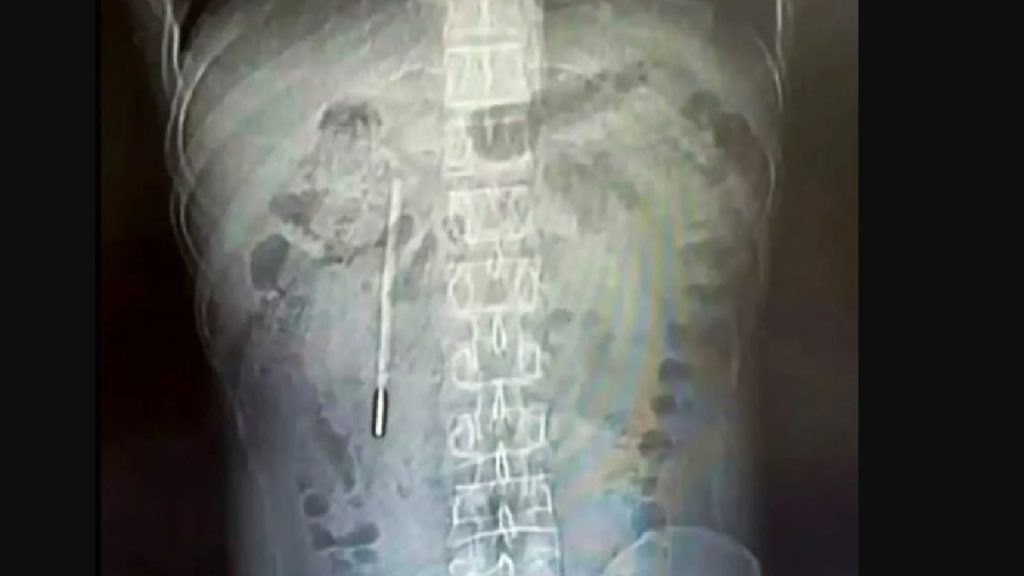

Un bărbat din China a trăit timp de 20 de ani cu un termometru în stomac, descoperirea fiind făcută abia recent, când a căutat ajutor medical pentru dureri abdominale persistente. Incidentul neobișnuit a avut loc în provincia ZHEJIANG, unde medicii au extras cu succes termometrul, înghițit accidental de bărbat în copilărie.

Wang, în vârstă de 32 de ani, a ajuns la spital acuzând dureri abdominale constante. Investigațiile medicale au condus la o descoperire șocantă: în duodenul pacientului se afla un termometru cu mercur. Obiectul era poziționat riscant, aproape de peretele intestinal, ceea ce ar fi putut provoca complicații grave precum perforații sau hemoragii interne.

Intervenția chirurgicală de urgență a fost necesară pentru a îndepărta termometrul, care s-a dovedit a fi intact, deși marcajele de pe el erau șterse. Medicii au subliniat șansa mare a pacientului de a nu suferi complicații grave de-a lungul celor două decenii. Cazul lui Wang readuce în atenție riscurile asociate cu obiecte străine înghițite accidental.